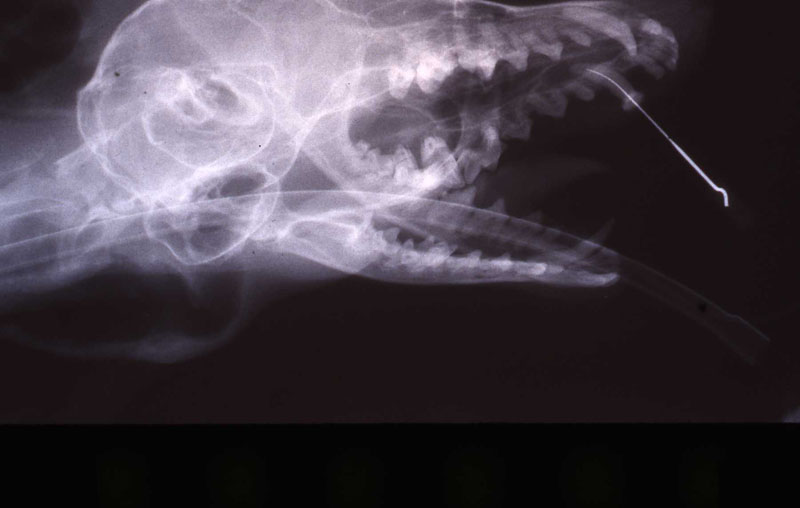

An 18 month old, 7.5 kg , female caracal (Caracal caracal caracal) new to the Milwaukee County zoo collection presented with a fractured right maxillary canine tooth during routine quarantine examination. The canine tooth had approximately 3 mm of its tip fractured off, the pulp chamber was exposed, and the tooth was darkened due to degeneration of of the pulpal tissue, and induction of food debris. There was no sign of an external drainage tract lesion. Radiographic examination revealed the presence of a periapical lesion 6mm by 7mm in diameter. The extra-oral surgical approach was chosen to debride the periapical lesion, resect the apex, and perform a retrograde fill in conjunction with the coronal or oblique endodontic fill.

lnteroperative and postoperative radiographs were obtained to verify endodontic working length and extent of endodontic fill.

The animal was reimmobilized using either a similar anesthetic regimen, or ketamine 6mg/kg and medetomidine (Domitor©, Pfizer Animal Health) 37 mcg/kg I.M., at 3 weeks, 14 months and 29 months. A small scar, approximately 1x4 mm, remains present at the incision site. Radiographs taken at each recheck showed healing of the periapical lesion, and normal bone repair in the surgical site.